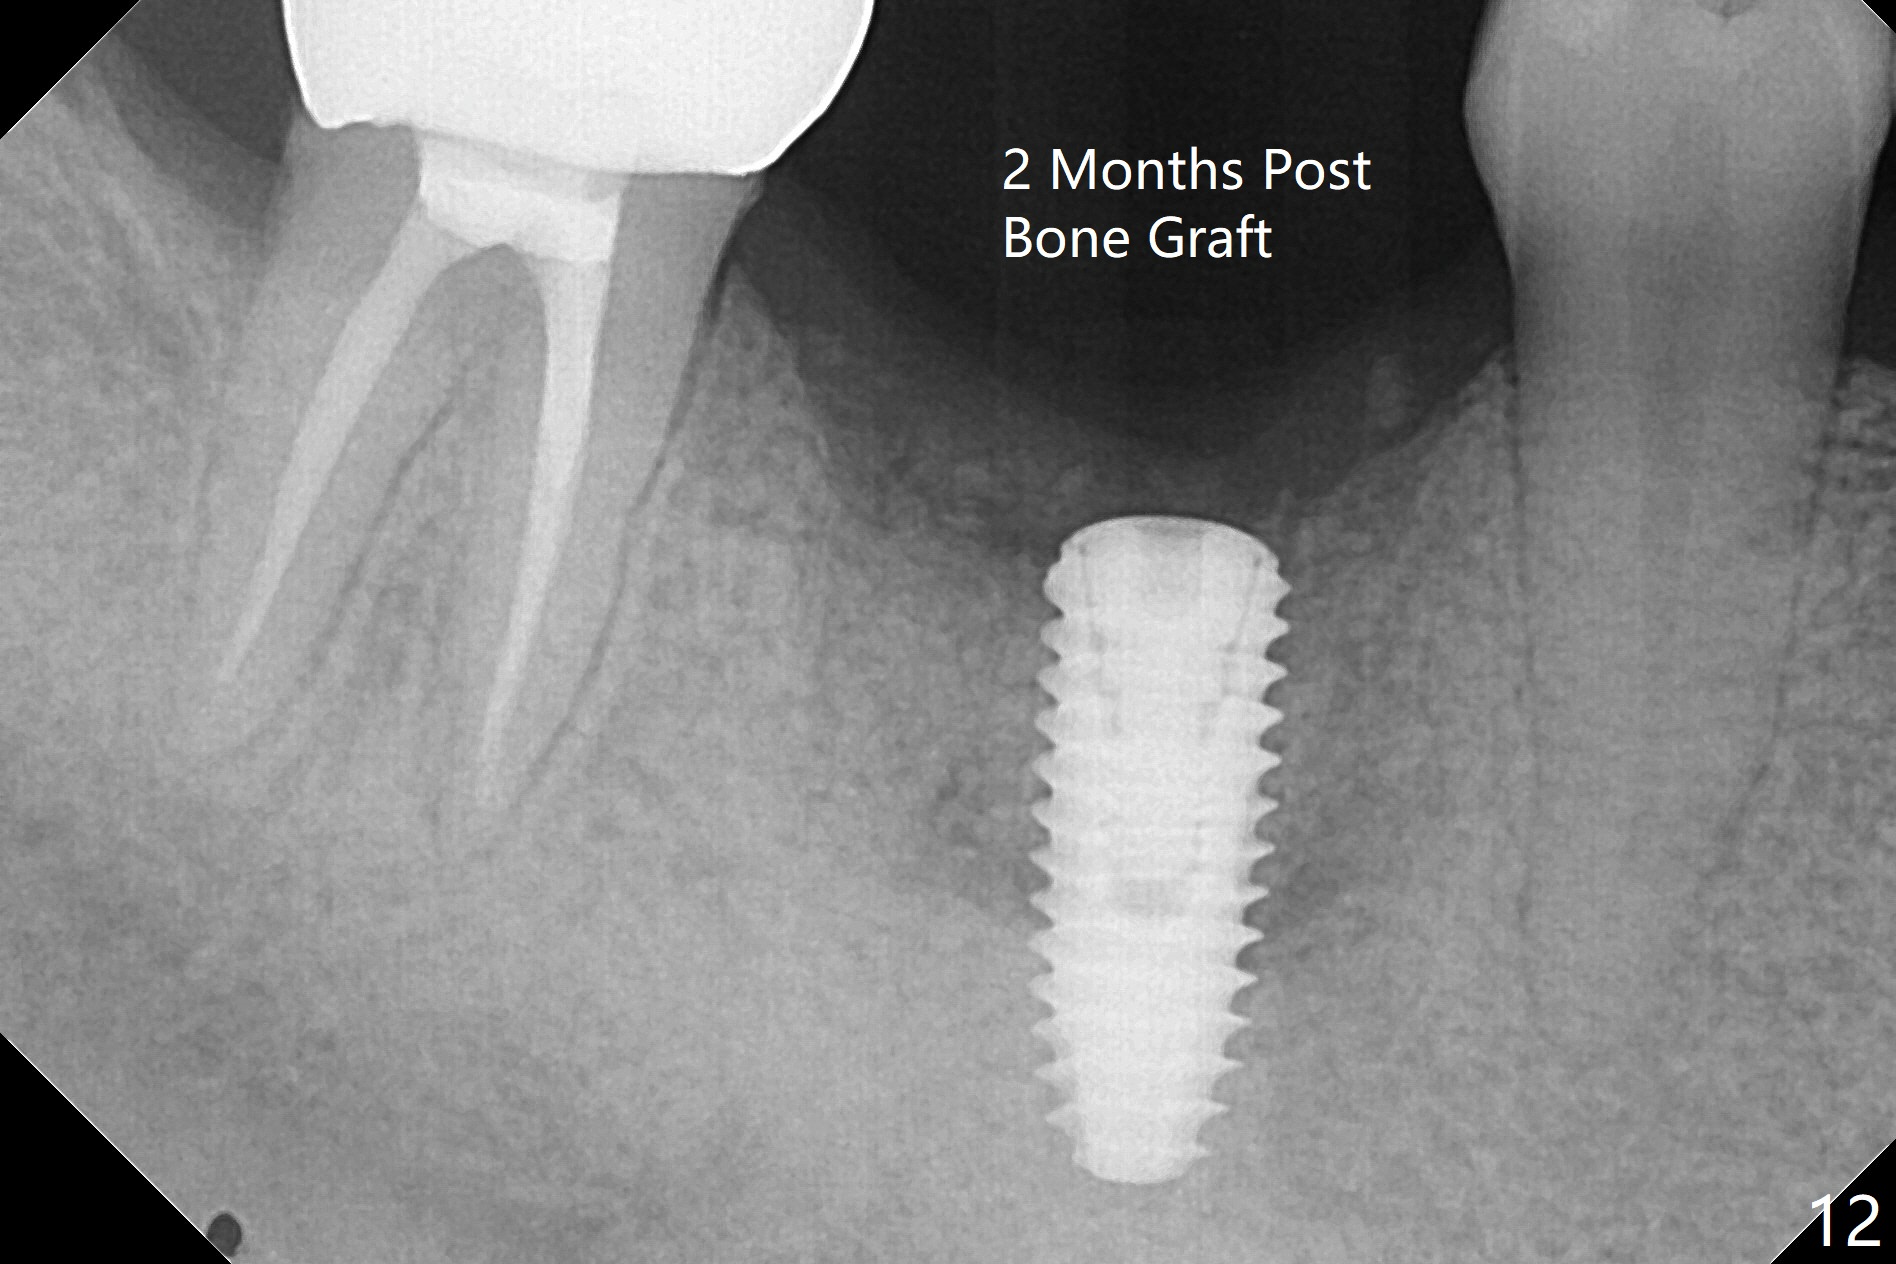

In spite of use of water pik, the coronal threads of the implant at #30 remain exposed 2 months postop (Fig.1). Envelop incision with mesial and distal accessory release ones reveals buccal bony defect (Fig.2). After 2nd spin (1500 RPM for 10 minutes), PRF forms in the red tube (Fig.3 yellow gel-like). Following use of Titanium brush, sticky bone is place (not so bone block-like, Fig.4), followed by a large piece of PRF membrane (from the red tube of Fig.3), Cytoplast (Fig.5,6 white porous) and a small piece of PRF membrane (from the white tube, next to the thin gingiva). The distal (Fig.6 D) and mesial (Fig.7 M) flaps are approximated (arrows without suture) as much as possible as well as lingual. 4-0 Polyglycolic Acid suture is used. Periodontal dressing dislodges 5 days postop. When the patient returns 1 week postop, he is pain free. Although Cytoplast is exposed, the surrounding gingiva seems to be healthy (Fig.8). Later the permanent crown of #31 is temporarily cemented with OHI. It appears that Cytoplast could be used to cover PRF membranes for soft tissue defect, followed by immediate provisional at the stage of immediate implant. The discolored (apparently contaminated) Cytoplast seems to be expelled 6 weeks postop (Fig.9). When the latter is removed, the soft tissue looks normal (Fig.10). Two weeks later, the apparently normal, but thin gingiva forms over the former granulation tissue (Fig.11 *, as compared to Fig.10). There is not enough bone coronal to the implant plateau 2 months post graft (Fig.12). Three months later, bone graft will be re-placed possibly with uncover.